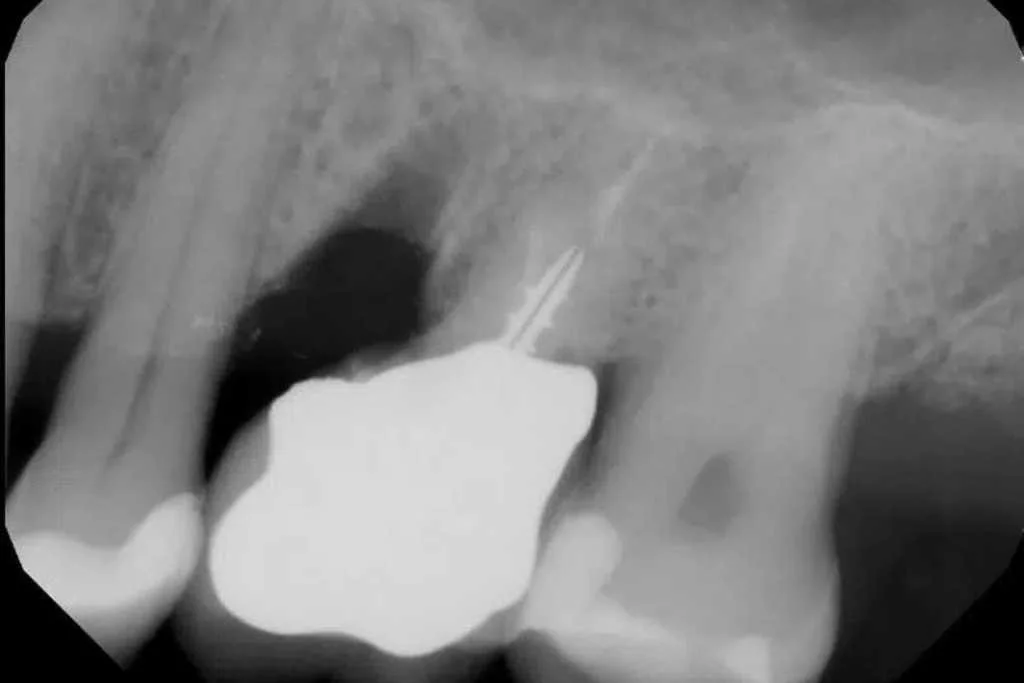

X-ray of a upper molar tooth with a root amputation that allowed the patient to keep the tooth and avoid a sinus lift and dental implant

X-ray image of a maxillary molar showing a root considered for maxillary root amputation.